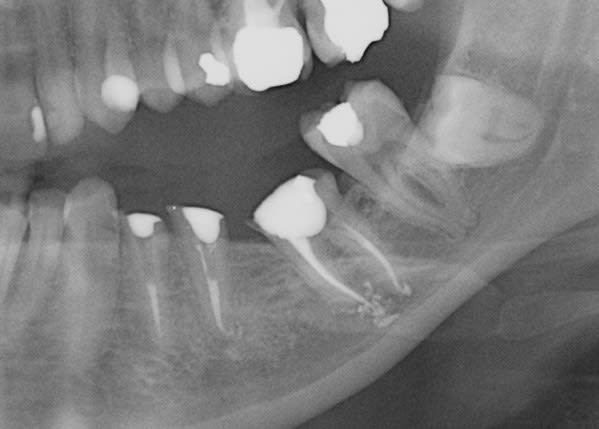

exemple d'endo sous tronculaire...